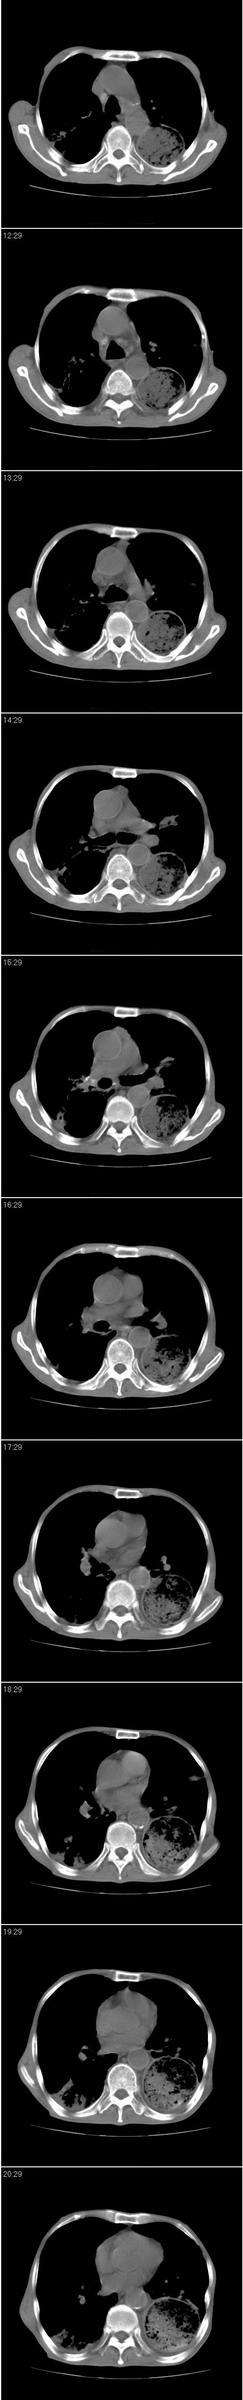

以下是引用andymaomao在2007-8-18 14:29:00的发言:[br][br]1.该患者应有食道ca手术史,胃位于左侧胸腔(后纵膈旁);[br]2.双肺继发性肺tb?!不排除部分病灶改变为转移灶;[br]3.纵隔气管旁可见肿大淋巴结;[br]4.右下侧后胸壁轻度增厚、粘连。[br]5.另左肺部分肺组织含气不良(受压!?)。[br][br]

以下是引用dyqct在2007-8-18 14:40:00的发言:[br]考虑:1、食道弓上吻合术后(左侧胸腔胃);[br] 2、右上继发型肺结核;[br] 3、慢性支气管炎合并全小叶型肺气肿、感染。